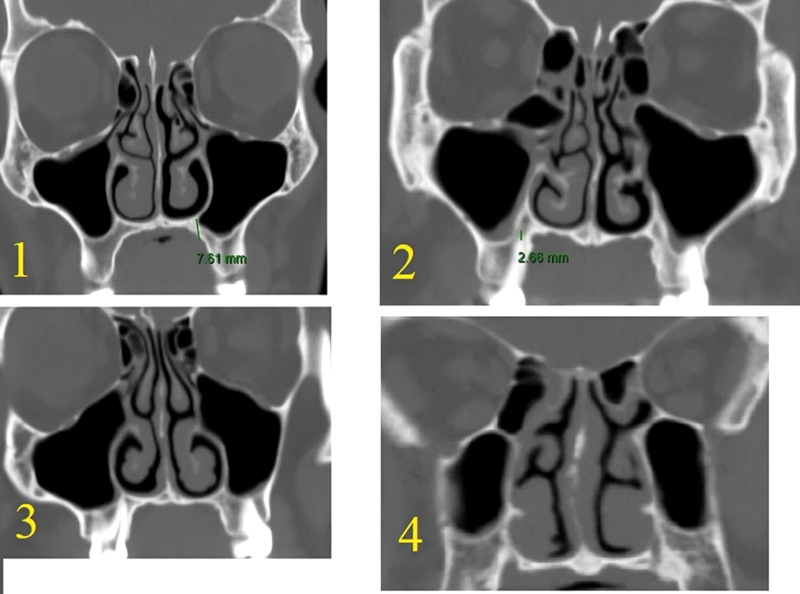

Introduction  The preoperative assessment of the computed tomography (CT) characteristics of the maxillary sinus helps to preserve its anatomical and functional integrity during and after surgery. Objective  To use CT scanning to identify maxillary sinus variations and types that were not previously published. Methods  The present study was carried out on 110 paranasal CT scans (220 sides). Axial images were obtained with multiplanar scans, to visualize details in coronal and sagittal planes for all subjects. Results  Among the 110 CTs (220 sides) of the maxillary sinus's floor, there were 53.2% type 1, 29.1% type 2, 10% type 3, and 7.7% type 4, with significant difference between genders. The most common maxillary sinus floor was type 1. The lateral maxillary sinus wall was found to be type 1 in 32.7%, type 2 in 65%, and type 3 in 2.3%, with a significant difference between genders. The most common lateral wall of the maxillary sinus type was type 2. The orbital floor was found to be type 1 in 0.9%, type 2 in 21.3%, type 3 in 50.5%, and type 4 in 27.3%, without significant difference between genders. Asymmetry was detected between the right and left sides for the maxillary sinus floor of in 22.7%, lateral maxillary wall in 16%, and orbital floor (maxillary roof) in 30%. Conclusion  This study aims to increase surgeons' awareness of maxillary sinus variations, creating new classifications for usage and communication in the otorhinolaryngology and endoscopic fields. It could also be helpful for training medical residents.

Abstract Image